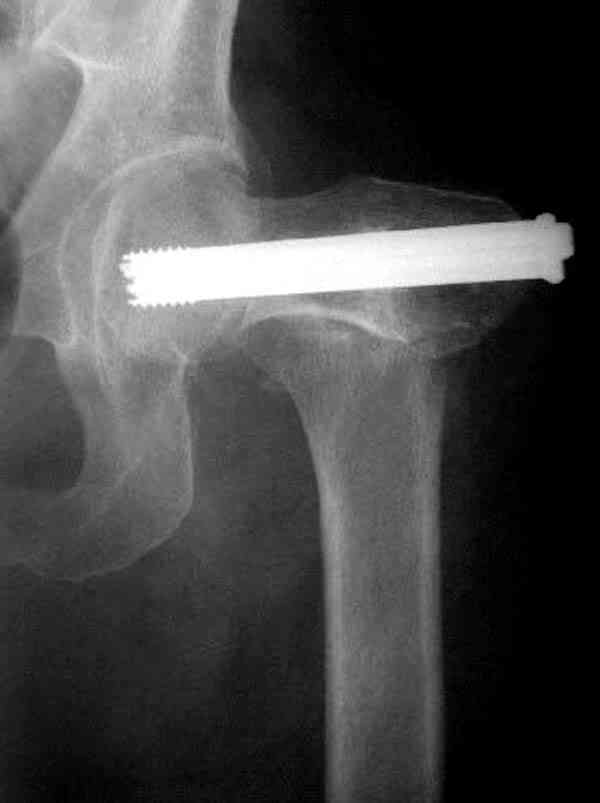

В идеале для профилактики рефрактуры шурупы надо вводить не больше, чем под 130 градусным углом и не ниже уровня малого вертела.

Насчет биомеханических преимуществ одного шурупа тоже возникает вопрос. Если придерживаться канонов механики, для перелома шейки необходимо 3 паралельных шурупа, расположенных ближе к кортикальному слою шейки.

Здесь случай перелома из-за ослабления латерального кортекса через 3 недели после операции на шейке. Шурупы были установлены под большим углом, слабый латеральный кортекс не выдержал нагрузку.